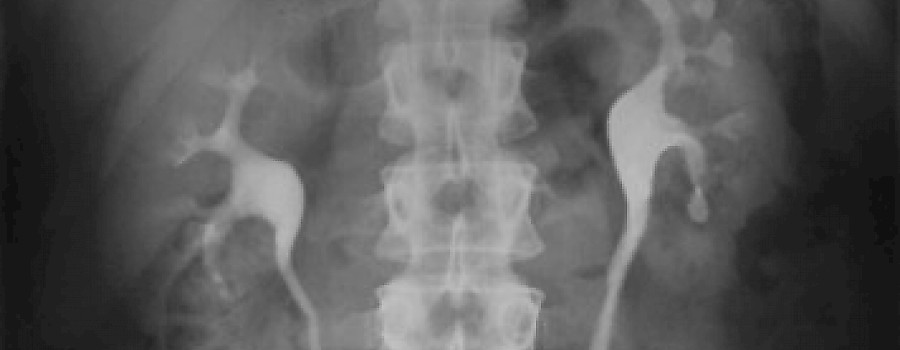

Was ist auf unserem heutigen ominösen Röntgenbild abgebildet?